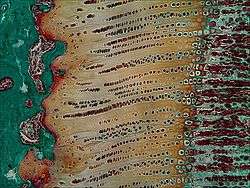

Histology

The growth plate has a very specific morphology in having a zonal arrangement.

| Epiphyseal plate zone (from epiphysis to diaphysis | Description |

|---|---|

| Zone of reserve | Quiescent chondrocytes are found at the epiphyseal end |

| Zone of proliferation | Chondrocytes undergo rapid mitosis under influence of growth hormone |

| Zone of maturation and hypertrophy | Chondrocytes stop mitosis, and begin to hypertrophy by accumulating glycogen, lipids, and alkaline phosphatase |

| Zone of calcification | Chondrocytes undergo apoptosis. Cartilagenous matrix begins to calcify. |

| Zone of ossification | Osteoclasts and osteoblasts from the diaphyseal side break down the calcified cartilage and replace with mineralized bone tissue. |